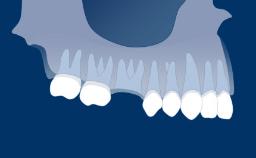

Introduction to Implant Dentistry

Loading Protocols

The moment when implants are put into function is marked by the connection of the implant prosthesis.

The choice of the most suitable loading protocol is an important step in the process of treatment planning. When selecting the moment of implant rehabilitation, you are faced with an important clinical decision.